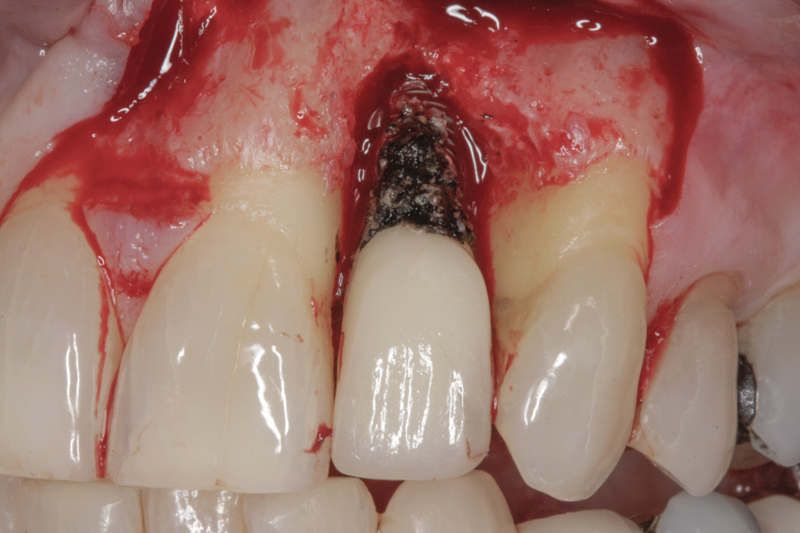

Current Understanding of Peri-implant Disease and Residual Excess Cement

Why implant cement should cause an issue is unclear, as is to what extent the cement plays a part in the process. It is possible that the cement is simply passive and acts as a physical bacterial trap—similar to an overhang on a restoration or calculus effects on the natural dentition (Figure 3). It is also possible that the cement plays a more active role because the destruction of both hard and soft peri-implant tissues is frequently aggressive and extensive (Figure 4 and Figure 5). The disease may be different between patients—and even within the same patient; it may be due to either one major primary factor or a combination of factors.

Figure 3

Figure 4

Figure 5